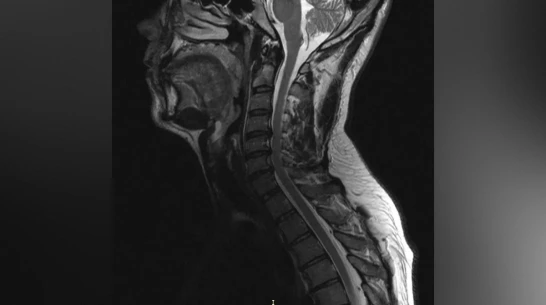

Пациент долгое время страдал от остеохондроза шейного отдела позвоночника. С августа 2025 года боль усилилась и распространилась на правую руку. Вместе с болью пришли слабость и онемение. В стационаре мужчине поставили диагноз – диско-остеофитный стеноз позвоночного канала. Это значит, что на уровне ряда шейных позвонков произошло сужение, а находящиеся в позвоночном канале структуры подверглись сдавливанию.

Через три часа после операции пациент уже мог вставать на ноги. Боль пошла на спад, в мышцы вернулись силы. Мужчину выписали на пятые сутки после операции. Однако его еще ждет лечение в отделении реабилитации.